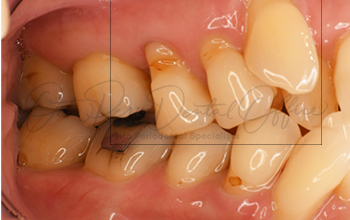

| 治療期間 | 6週間 |

|---|---|

| 治療費 | 13万 |

| 治療内容 | 左下小臼歯(4,5) 根面被覆(結合組織移植術) |

| 治療のリスク | ドナーサイトが必要、 術後の疼痛・腫脹、術後の注意事項をフォローしない場合は失敗の可能性あり |